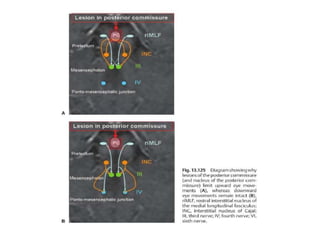

Anatomy of conjugate vertical gaze

Conjugate Vertical eye movement

Post.

commissure

Down gaze paresis

Anatomy of conjugatevertical gaze